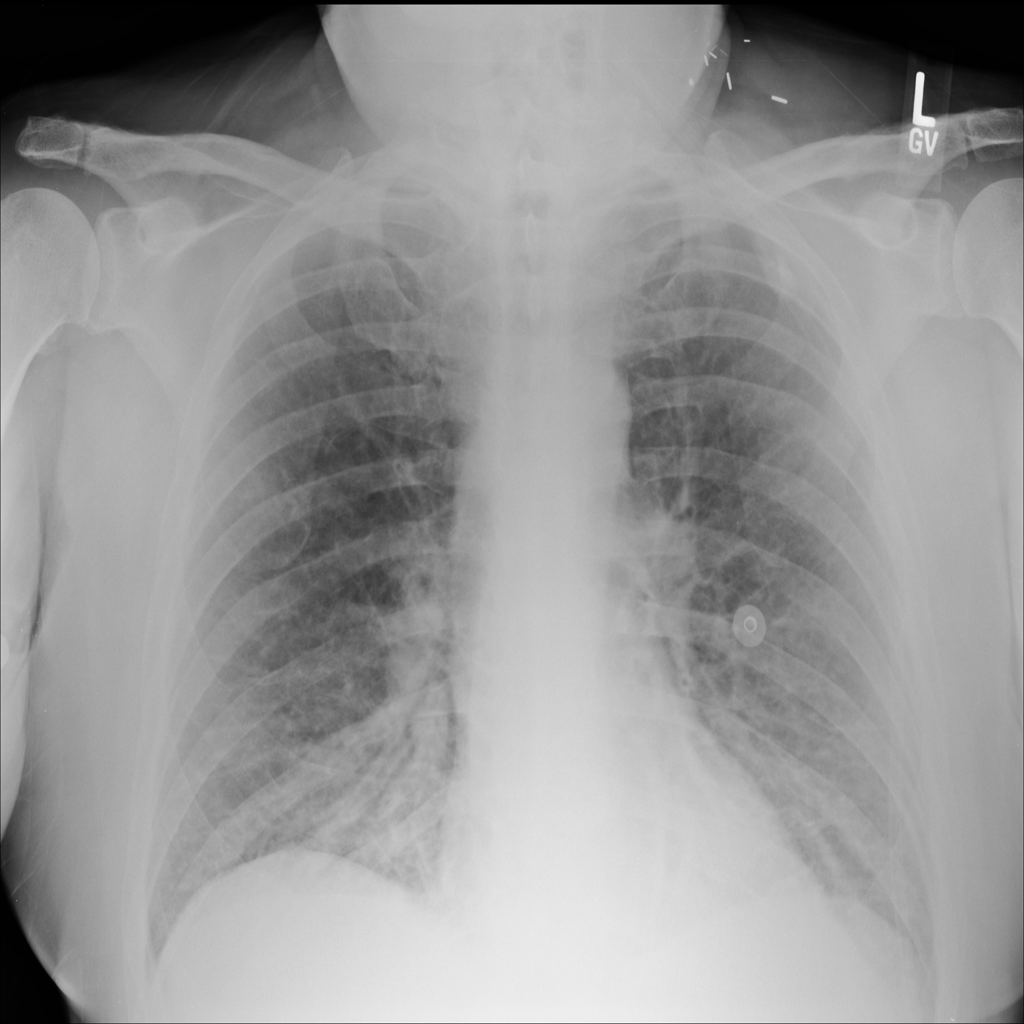

PAT-5B86 · IMG-009Edema

PAT-5B86 · IMG-009

PA